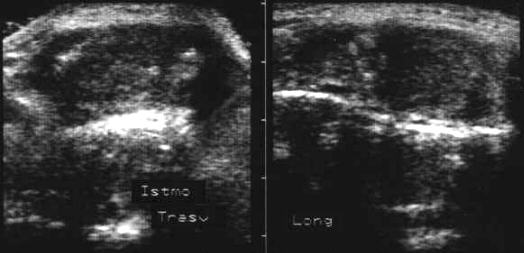

Lob drept, proiectie trasversala. Lob

stang, proiectie trasversala.

Lob drept, proiectie longitudinal. Lob stang, proiectie longitudinala.

Femeie de 41 ani. Tiroida de consistenta dura, foarte

dureroasa la palpare, cu suprafata neregulata.

Ecografia: moderata crestere a volumului; marginile lobilor rau definite; structura

intens ne mogena cu alternanta de arii hipoecogene, de edem si altele intens ecogene,

cu aspect pseudonodular.

Examene de laborator: moderat hipertiroidism; indici de fibroza foarte ridicati.